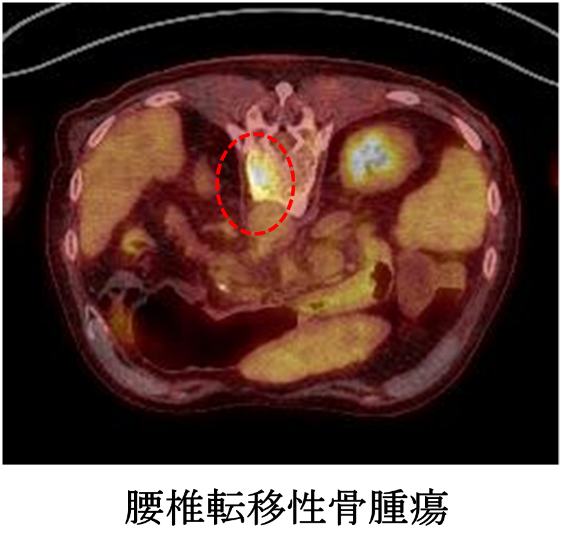

骨や軟部組織(筋肉、脂肪組織など)に発生する腫瘍を骨軟部腫瘍と呼びます。整形外科腫瘍班は骨軟部腫瘍を専門的に治療しております。また、肺癌や乳癌などほかの臓器に発生したがんが骨に転移した転移性骨腫瘍についても他科と連携して治療を行っております。

転移性骨腫瘍は、骨の痛みや病的骨折、脊髄麻痺の原因となり、がん患者さんの日常生活に大きな影響を与えます。転移性骨腫瘍の治療は原発巣の治療を行う主治医との連携と、腫瘍に対する幅広い知識が不可欠です。しかし、腫瘍を専門とする整形外科医は少なく、適切な治療を適切な時期に受けられないこともあります。我々は主治医とともに積極的に転移性骨腫瘍の診療に参加し、がん患者さんが失ってしまった日常を取り戻せるよう、また、現在の日常を失わないようにサポートしております。